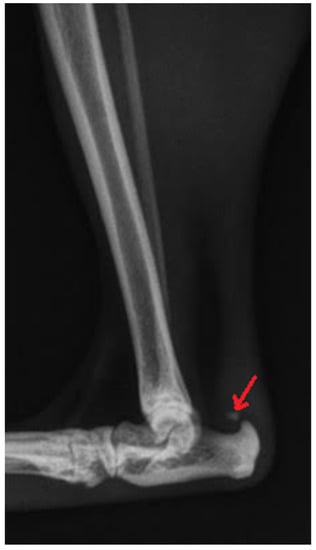

Radiography can be used for the indirect imaging of Achilles tendon injuries, but its usefulness is limited due to the superimposition of bones and poor contrast, as well as the structure visibility of soft tissues [1,40]. Radiographs can only show the foci of tendon mineralization and the swelling of adjacent soft tissue (Figure 1) [40,43]. Computed tomography (CT) is a cross-sectional imaging modality and has improved the identification of pathological lesions of the calcaneal tendon, such as enthesopathies and tendinopathies. CT provides sectional images; therefore, it eliminates the problems of superimposition correlated with conventional radiology. Achilles enthesopathy is defined as abnormality of the tendons and their attachment to the calcaneal tuber (Figure 2 and Figure 3).

Figure 3. CT 3D image reconstruction of the mineralization of the Achilles tendon (arrow).